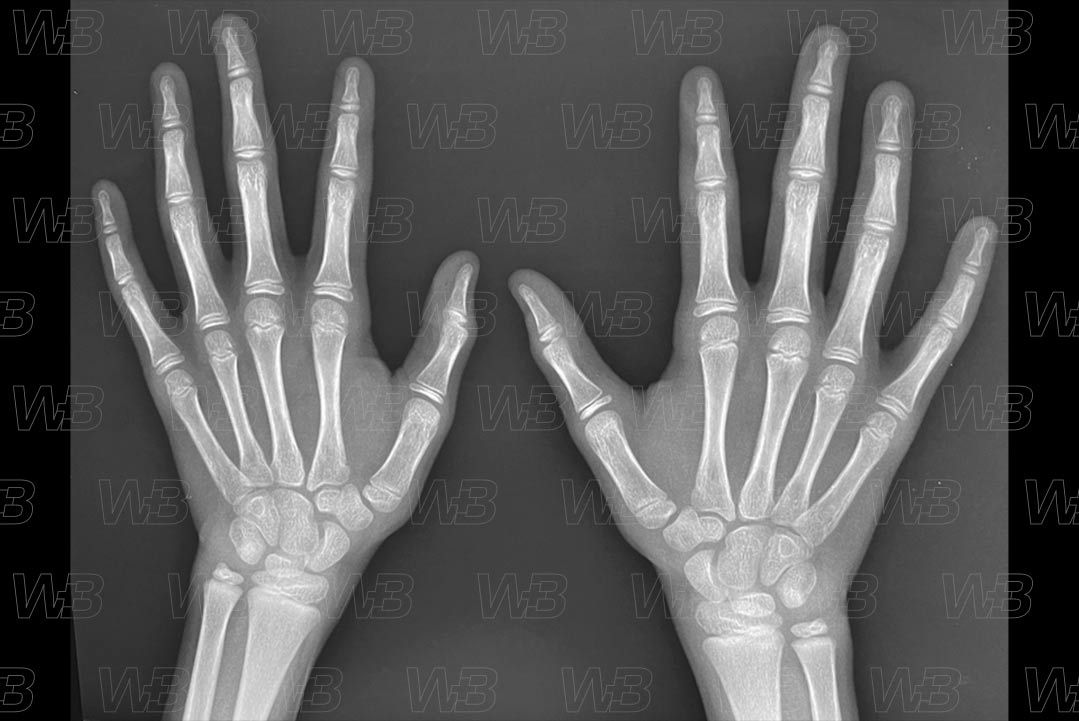

RADIOGRAFIA MÃOS E PUNHOS (IDADE ÓSSEA) [cms-watermark]

Feminino

10 anos:

• Hâmulo do hamato;

• Epífises das falanges média e proximal do quinto dedo são largas como as metáfises.